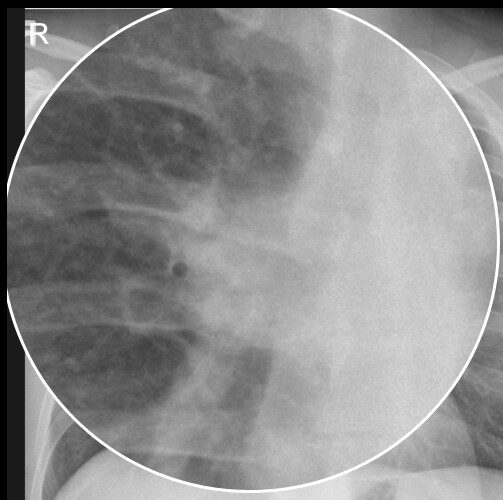

Radiologische Kontrolle von Herzschrittmachern und ICDs

Herzschrittmacher (SM) und implantierbare Cardioverter-Defibrillatoren (ICD) sind fester Bestandteil der Therapie von Herzrhythmusstörungen. Die Radiologie spielt dabei eine zentrale Rolle […]